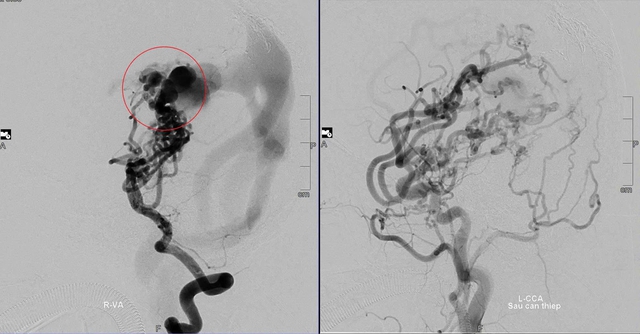

Khối dị dạng mạch máu não của bé D. trước và sau nhiều lần can thiệp.

Khi bé D. vừa tròn 1 tuổi, TS.BS Trần Chí Cường đã thực hiện ca can thiệp đầu tiên tại Đà Nẵng. "Đây là thử thách rất lớn. Khối dị dạng quá phức tạp, trong khi bệnh nhi lại còn quá nhỏ và dụng cụ can thiệp hạn chế" - chuyên gia chia sẻ.

May mắn, ca đầu tiên thành công ngoài mong đợi. Các bác sĩ hội chẩn và quyết định sẽ can thiệp nhiều giai đoạn để giảm lưu lượng máu, ngăn nguy cơ vỡ khối dị dạng.

"Suốt 10 năm, bé D. đã trải qua 8 lần can thiệp mạch não. Từ chỗ yếu liệt, khó khăn trong vận động và ngôn ngữ, bé D. đã có thể đứng và đi vững khi lên 3 tuổi rưỡi. Giờ đây, em học tập, vui chơi bình thường như bao bạn bè đồng trang lứa.